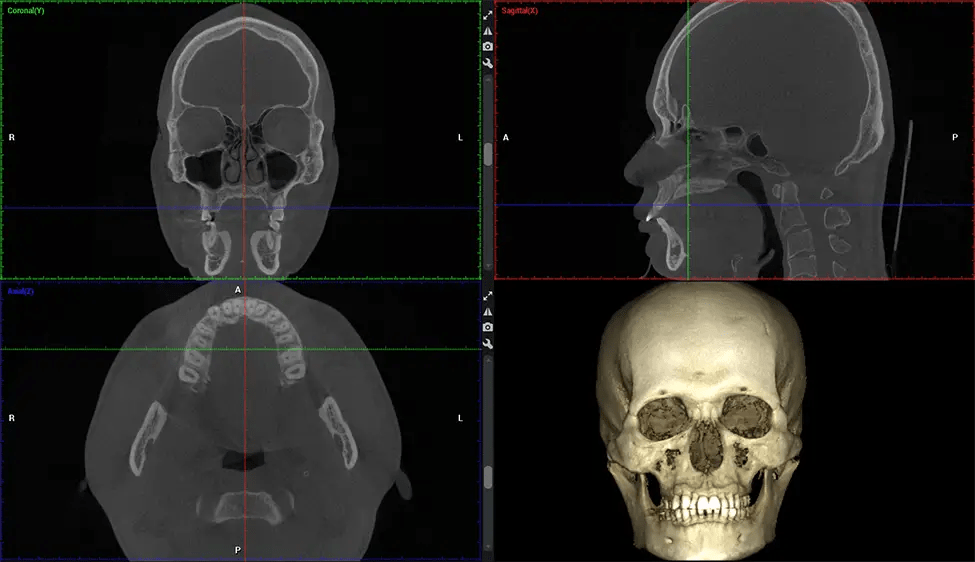

Cone Beam Computed Tomography (CBCT) is an advanced imaging technique used in dentistry and maxillofacial surgery to obtain detailed 3D images of the oral and maxillofacial structures. At Dr G Dental Studio, our CBCT scanners utilize a cone-shaped X-ray beam and a specialized detector to capture images from different angles. A computer then combines these images to create a 3D representation of the patient’s oral anatomy.

This 3D scan, called cone beam computed tomography, gives your dentist a more complete image of your oral anatomy and disease processes than a traditional X-ray. Unlike conventional X-rays, which capture a 2D image of your mouth from various angles, a 3D scan takes multiple digital X-rays for one image. It provides a complete view of your jaw, teeth, nerves, and soft tissues. This enhanced view allows dentists to detect minor issues not visible in traditional 2D scans, such as impacted wisdom teeth or bone fractures in the sinus cavity.

There are many benefits to using CBCT technology, especially compared to the traditional 2D X-ray format. One of the most significant advantages of CBCT scans is that they provide much more information than traditional X-rays. A scan lets your dentist see images from all angles of your jaw and mouth, including your sinuses, nasal cavity, cheekbones, and other surrounding areas. This added information helps your dentist craft a comprehensive treatment plan that addresses all aspects of your oral health.

Planmeca Viso G7 CBCT ( Cone Beam CT Scan ) is designed to surpass the demands of industry leaders, specialists, and large institutions. It’s has a large ø25×30 cm sensor with four built-in cameras. It can capture unlimited volume sizes from a ø3×3 cm to a ø30x30cm volume capturing the skullcap through C7 on the cervical spine. The Planmeca Viso G7 offers the industry’s largest single volume scan of ø30×19 cm. It’s poised to handle advanced imaging modalities such as Planmeca ProFace® and Planmeca 4D™ Jaw Motion technology. The occipital head support allows an unimpeded view of facial tissue.